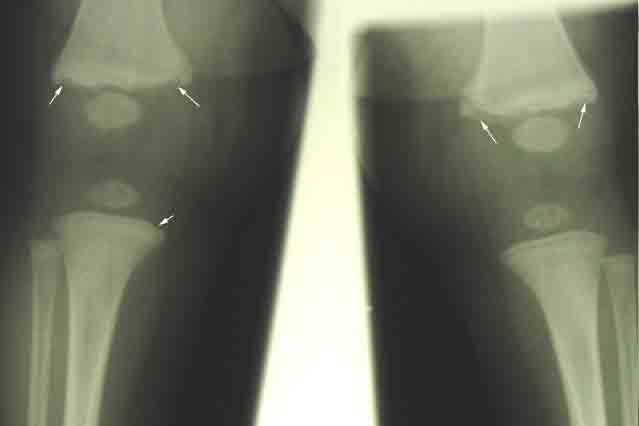

Classic metaphyseal lesions - bucket handle fractures and corner fractures (white arrows) in a 9-month-old child.

(Photo courtesy of Children’s Hospital Boston Child Protection Team.)